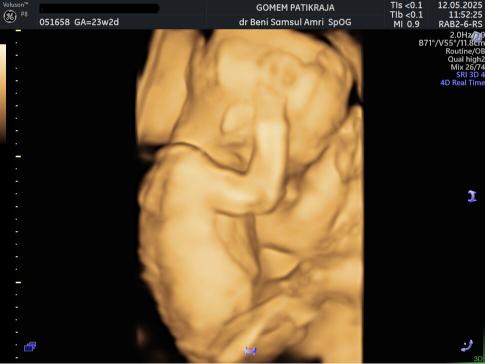

USG Janin 23 Minggu

Perkembangan Janin 23 Minggu:

Perkembangan otak janin melesat cepat, ia kini sudah bisa bermimpi di dalam kandungan. Lapisan vernix caseosa yang melindungi kulitnya mulai menebal sebagai persiapan lahir. Ukuran tubuhnya kini sebanding dengan buah melon besar.